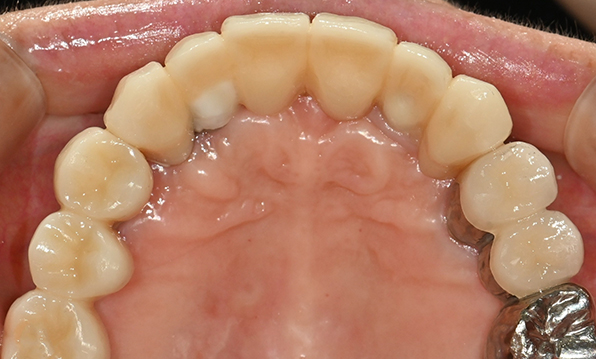

Case 02

Before After